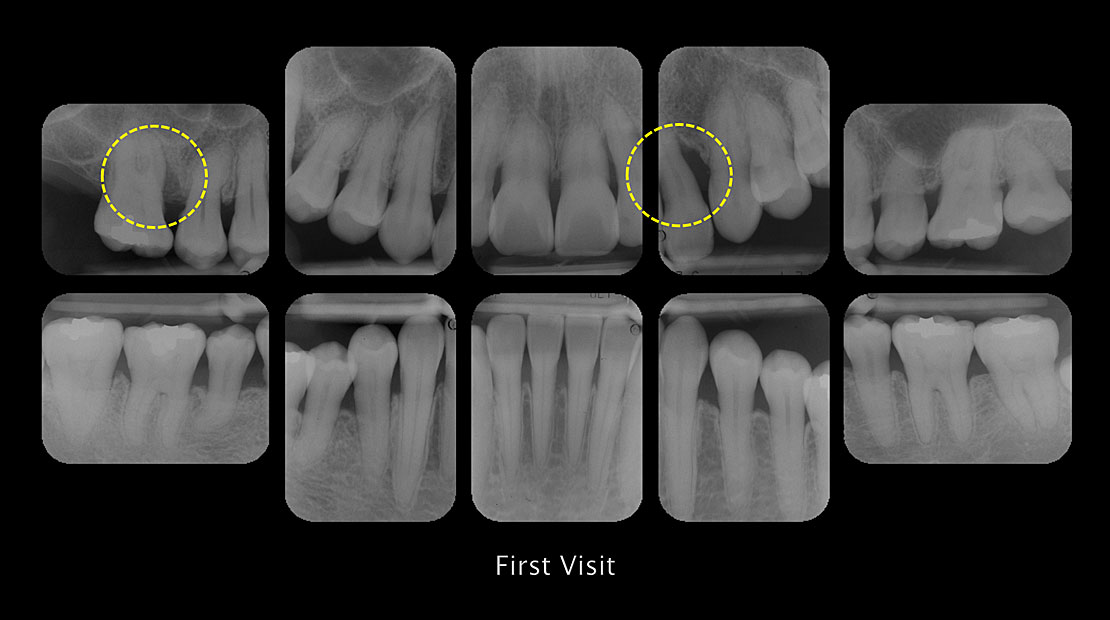

図2,3 重度歯周病患者おける水平的骨吸収と細菌叢バランス

いわゆる全顎的に水平骨吸収を伴う重症歯周病患者の菌叢バランスは、本講演中に紹介したRed 10 および Red 10 plus の分布は著しく、病態と連動しているため、Inflammation Phenotypeと診断して間違いはないだろう。歯周基本治療は、歯科衛生士の技量が、その成否を決定的なものにするため、熟達した者でなければならないのは当然の事である。ソフト面でも、歯科衛生士による医療面接も、治療を進めるうえで重要な戦術であることに疑いの余地はない。抗菌療法の是非については、改めて議論することが大切であるが、重症患者における早期使用は、効果的な治療選択の一つである。